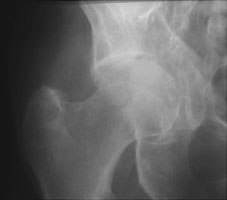

- Click on the image for a larger versionAAP radiograph of the right hip. This shows a comminuted fracture of the acetabulum.